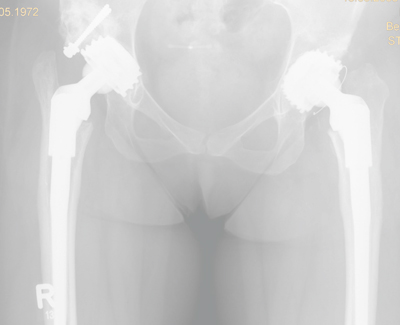

Hüfte

Fehlanlage des Hüftgelenkes ( Dysplasie )

Die unvollständige Ausbildung des Hüftgelenks ist eine der häufigsten angeborenen orthopädischen Erkrankungen. Mädchen bzw. Frauen sind davon häufiger betroffen als Jungen bzw. Männer. Wird sie im Säuglingsalter und in der Kindheit nicht ausreichend behandelt, treten im meist jungen Erwachsenenalter erste Beschwerden auf. Diese sind Ausdruck beginnenden Verschleisses, da Hüftkopf und Gelenkpfanne nicht schlüssig zueinander passen. Im Verlauf der Erkrankung entsteht eine Arthrose. Um diese möglichst lange hinauszuschieben oder gar zu vermeiden, besteht anfänglich die Möglichkeit, eine Umstellungsoperation des betroffenen Knochens (Becken- oder Oberschenkelknochen) durchzuführen. Bei fortgeschrittenem Verschleiss ist die Versorgung mit einer Endoprothese notwendig.